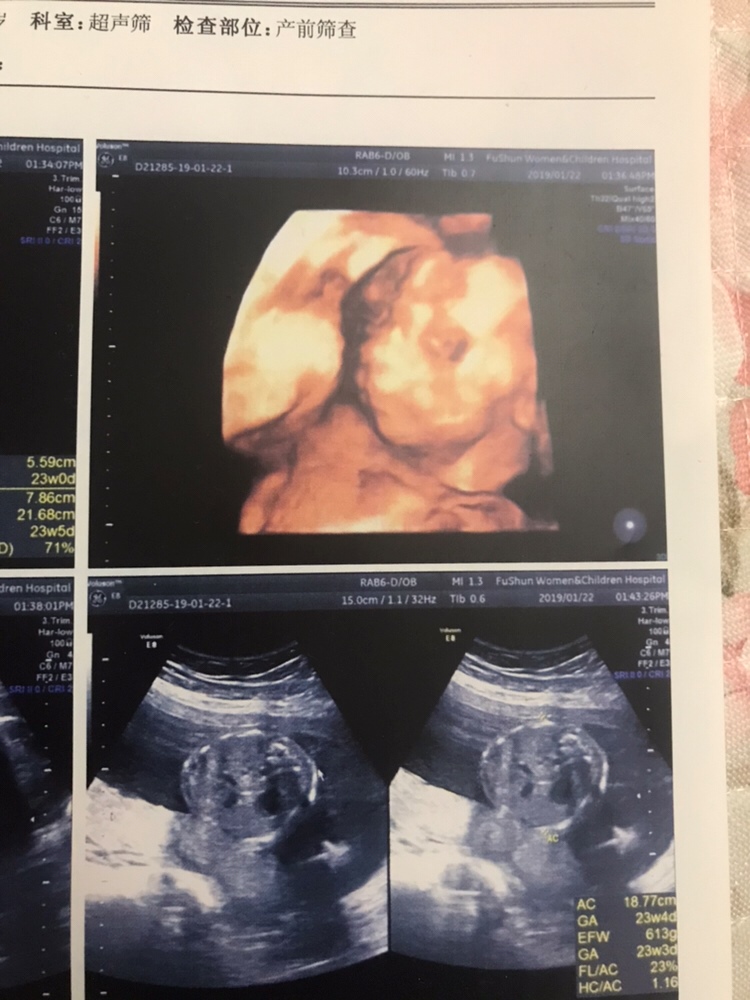

我的四维也做了,感觉拍出来的都差不多

Y.an[帖主]:勉强能看出鼻子、眼睛、嘴😅

拍的不好 怎么看

Y.an[帖主]:真是不咋地😓